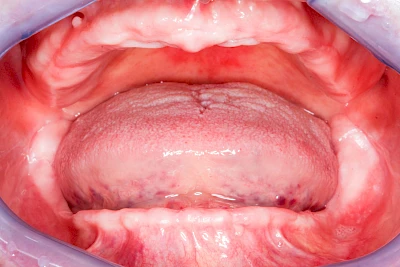

Lippen-Kiefer-Gaumenspalte

Lippen-Kiefer-Gaumenspalten (LKG-Spalte) sind angeborene Fehlbildungen im Mund-Kiefer-Gesichtsbereich. Die Gewebestrukturen im Bereich des Oberkiefers sind im Zuge der Entwicklungen bis zur Geburt nicht zusammengewachsen. Diese Fehlbildung zählt zu den häufigsten Fehlbildungen des Menschen, von 500 Neugeborenen ist eines betroffen. Die Fehlbildungen können sich auf Lippe, Gaumen und Kiefer allein beschränken, treten häufig aber kombiniert und in seltenen Fällen sogar beidseits auf.

Heute werden in Deutschland Menschen mit Lippen-Kiefer-Gaumenspalten bereits ab Geburt von Experten verschiedener Fachrichtungen (Mund-Kiefer-Gesichtschirurgen, Kieferorthopäden, Logopäden) betreut, damit entsprechende Korrekturen schon frühzeitig erfolgen können. Gerade jedoch bei älteren Menschen ist dies nicht immer geschehen. Diese Menschen tragen häufig technisch aufwendige Zahnprothesen.